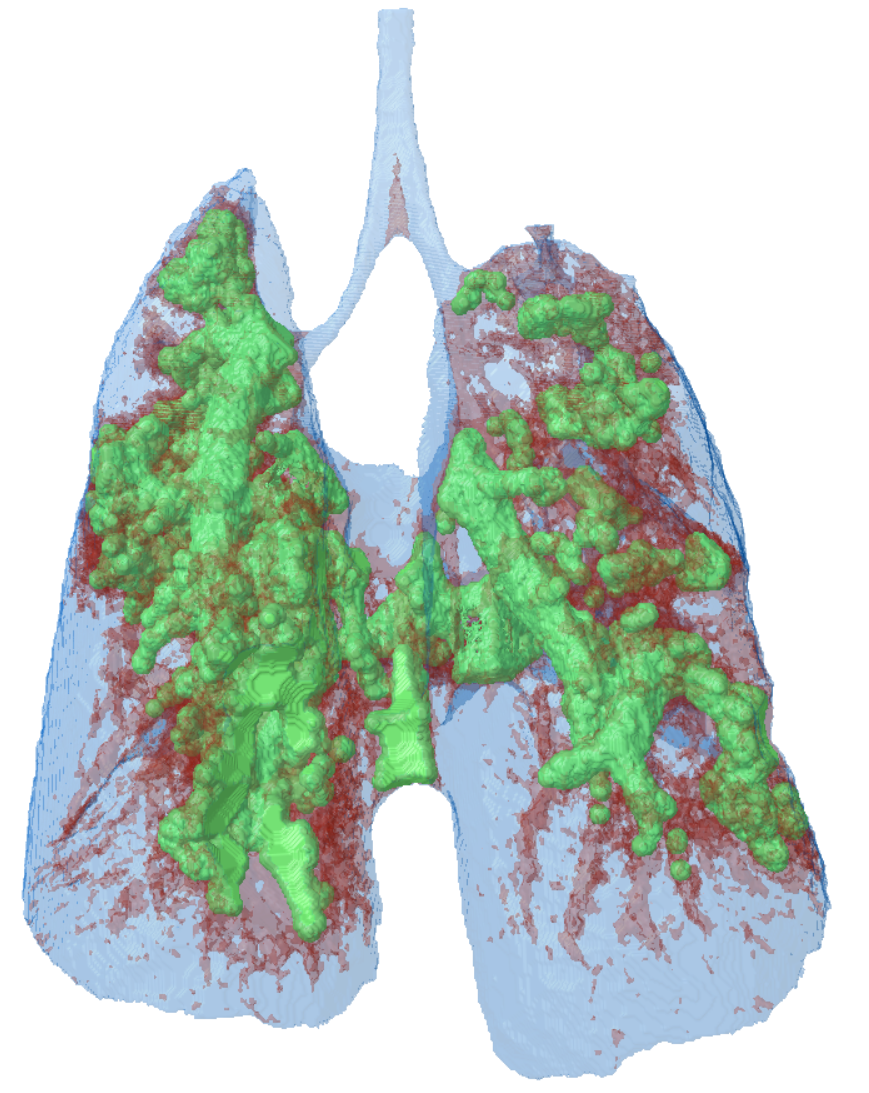

The SKYSCAN 1276 is a flexible high-performance lung imaging solution. Sharply time-gated lung images are obtained in short scan times with safe levels of ionizing radiation. In the same scanner there is ex vivo sample scanning capability at a voxel size down to 2.8 micron true resolution allowing imaging lung tissue at the alveolar level of architecture for advanced lung disease characterization.

3D model of a mouse lung, made transparent to visualize the lung tumour tissue in green.